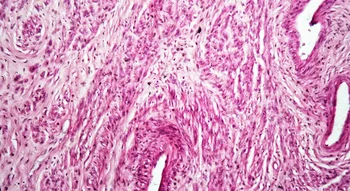

Aussi appelé « plancher pelvien », le périnée est un ensemble de muscles, de tissus et de ligaments en forme de hamac situé au niveau de l’entrejambe. Il recouvre la paroi inférieure du pelvis (petit bassin) entre l’os du pubis (symphyse pubienne) et le coccyx.

1. Pubis / 2. Coccyx / 3. Périnée superficiel / 4. Périnée profond

A. Clitoris / B. Méat urinaire / C. Vagin / D. Anus